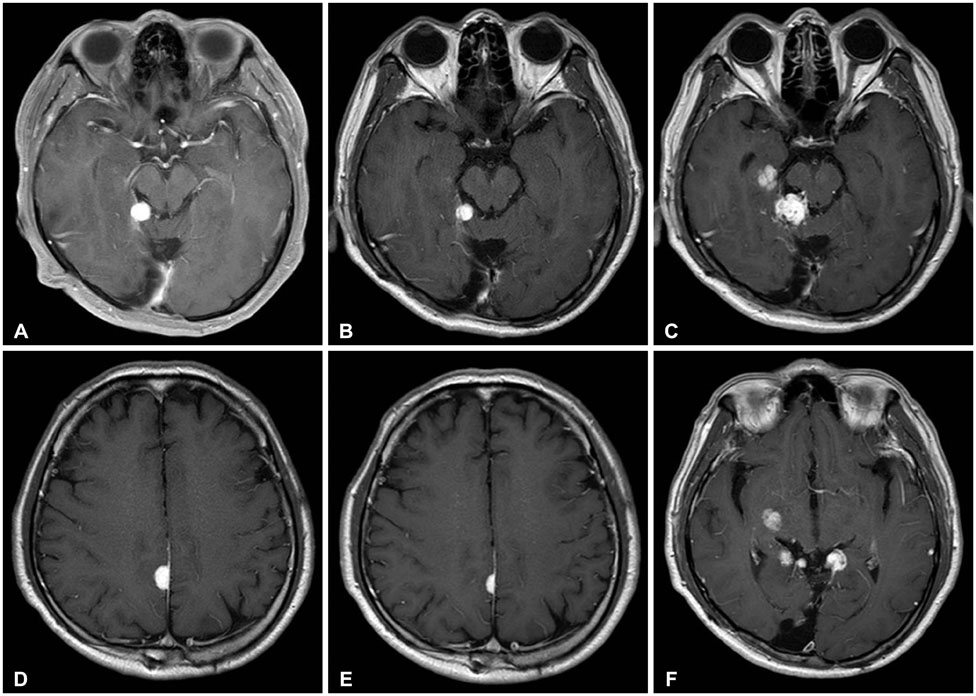

- Hemangioblastoma (HB) of the central nervous system may occur sporadically or in association with von Hippel-Lindau (VHL) disease. Disseminated HB means malignant spread of the original primary HB without local recurrence at surgically resected site. It has been rarely reported previously, and rarer especially without VHL gene mutation. We report a case of disseminated HB without VHL disease. A 59-year-old man underwent a surgery for total removal of a cerebellar HB. From five years after the surgery, multiple dissemination of HB was identified intracranially and he subsequently underwent cyberknife radiosurgery. The lesions got smaller temporarily, but they soon grew larger. Nine years after the initial surgery for cerebellar HB, he showed severe back pain. His magnetic resonance image of spine revealed intradural extramedullary mass at T6-7 level. Complete surgical removal of the mass was performed and the pathological diagnosis was identical to the previous one. He had no evidence of VHL disease. And there was no recurrence of the tumor at the site of the original operation. The exact mechanism of dissemination is unknown, but the surgeon should be cautious of tumor cell spillage during surgery and prudently consider the decision to perform ventriculo-peritoneal shunt. In addition, continuous follow-up for recurrence or dissemination is necessary for patients even who underwent complete removal of cerebellar HB.